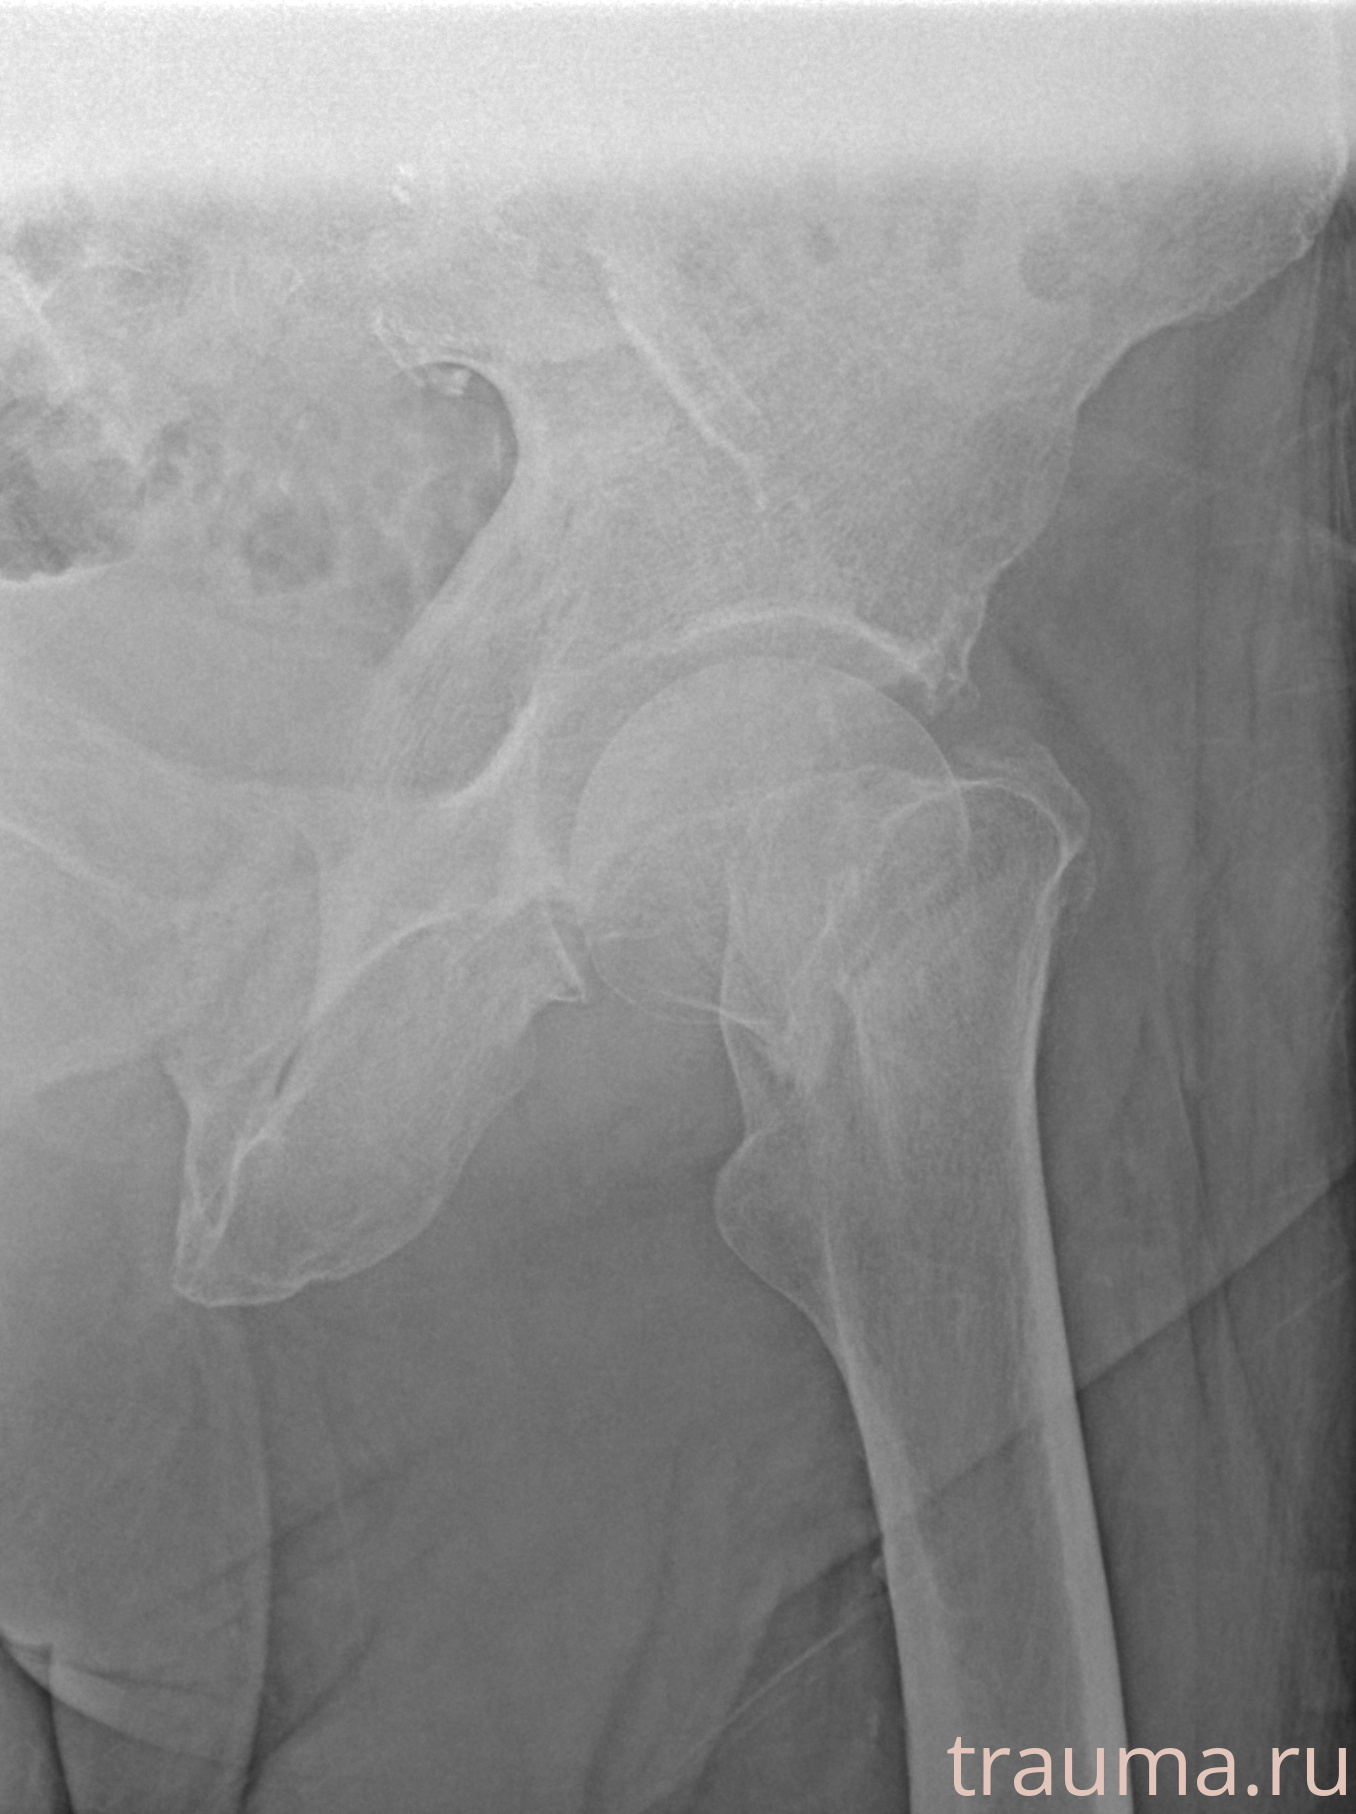

Рентгенограммы

Рентген на дому: по вашему адресу приезжает врач-рентгенолог, травматолог-ортопед с мобильным рентгеновским аппаратом, проводит диагностику травмы или заболевания, делает необходимые рентгенограммы, дает рекомендации по дальнейшему лечению. Получить качественные снимки в домашних условиях возможно благодаря уникальной методике, разработанной МосРентген Центром для института  Склифосовского